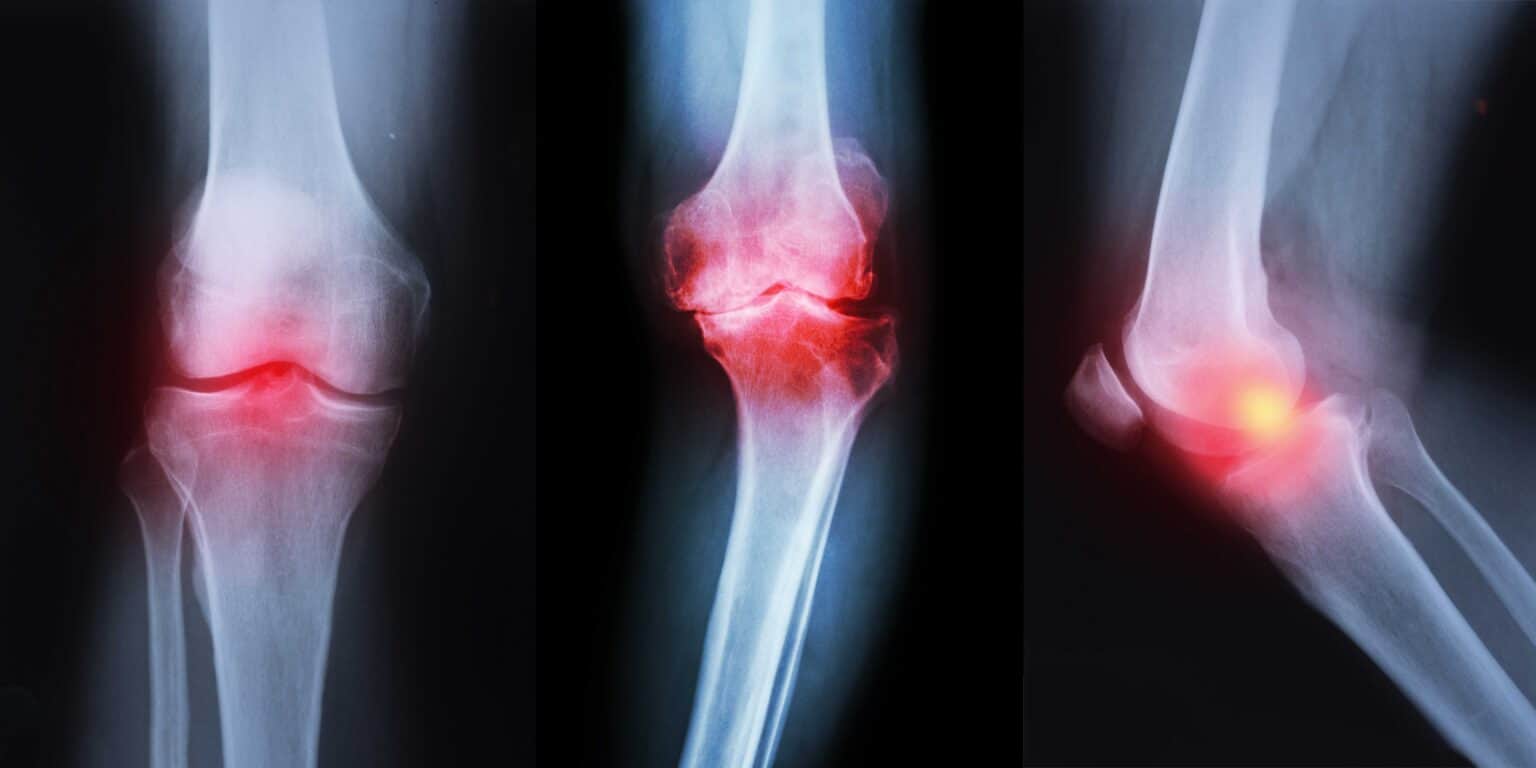

What is osteoarthritis (OA) of the knee? Complete Physio

Can Knee Arthritis Cause Neuropathy . Read about these 7 neuropathy symptoms. Rheumatoid arthritis (ra) can cause numbness and tingling. A growing amount of evidence suggests that the pain in oa has a neuropathic component in some patients. Although there is no cure for knee arthritis, there are steps you can take that. These could be signs of neuropathy, a condition linked to diabetes, medications and more. Arthritis of the knee can be a serious, debilitating disease. Peripheral neuropathy can be caused by health conditions such as diabetes, rheumatoid arthritis, lupus, kidney disease,. An inflammatory, autoimmune disease that mainly affects the joints, ra inflammation can. Neuropathy can happen due to lupus, rheumatoid arthritis, sjögren syndrome, vasculitis and more.